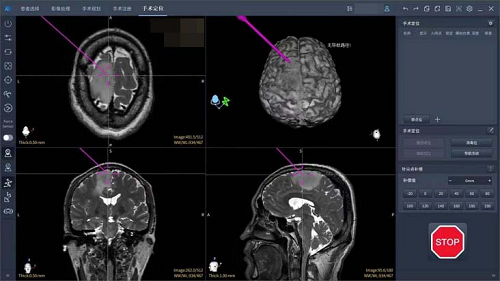

在本次手术中,朝阳医院神经外科副主任刘长青教授团队采用机器人辅助的术中导航技术,精准锁定肿瘤的边界。同时,结合术中脑电监测技术,通过皮层电极明确运动区的范围以及癫痫放电的范围,团队能够清晰了解肿瘤、癫痫灶与运动皮层的关系,从而确保在切除肿瘤及癫痫灶的过程中不损伤患者的运动功能。术中监测技术极大地提高了手术的安全性,尤其适用于像这位年轻患者一样,对运动功能有高度要求的病例。

借助机器人导航与脑电监测的双重技术保障,刘长青团队在保障精准的前提下,显著缩短了手术时间,并成功实现微创操作。术后,患者运动功能未受影响,恢复迅速,第3天便可下地行走,7天出院。该手术不仅成功切除了肿瘤和癫痫灶,还最大限度地保留了患者的运动能力,为今后的生活质量提供了有力保障。